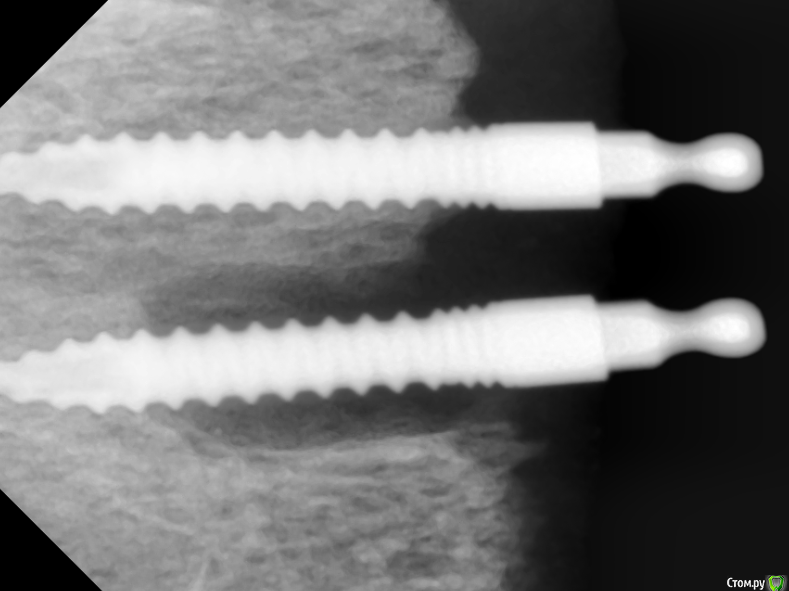

Sergiosse Опубликовано 14 июня, 2016 Поделиться Опубликовано 14 июня, 2016 (изменено) Не знаю как добавить фото в ранее созданую тему, поэтому создал новую.3 года назад установлены 4 цельных импланта остем для фиксации ПСП на в.ч. Сейчас на плановом осмотре импланты стабильны,жалоб нет в обл. 15 импланта свищь с отделяемым,н а снимке вертикальный очаг деструкции на 2/3 длинны импланта.С импл. в обл. 14 все окей. Гигиена отличная,использует ирригатор. Промыл хлоргексидином. Какая дальнейшая тактика? В чем причина.с нимок выложу позже. Изменено 14 июня, 2016 пользователем Sergiosse Ссылка на комментарий